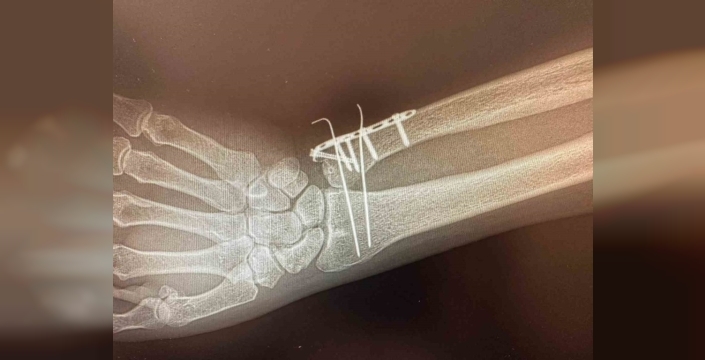

C Kollu Skopi cihazı sayesinde, hastanede ortopedi uzmanı Halil Sami Postallı'nın liderliğinde kemik ameliyatlarına başlandı. Bu yeni cihaz, ameliyathane ortamında hastaların iç yapısını anlık ve hareketli olarak görüntülemekte, böylece cerrahların daha doğru ve hızlı müdahalelerde bulunmasına olanak tanıyor.

C şeklindeki yapısı sayesinde her açıdan görüntü alabilen bu taşınabilir röntgen cihazı, ortopedi, travmatoloji, beyin cerrahisi, üroloji ve kardiyoloji alanlarında yüksek çözünürlükte görüntü sağlayarak ameliyatların güvenliğini artırıyor. Özellikle kırıkların düzeltilmesi, vida ve plak uygulamaları ile kalça ve diz protez ameliyatlarında etkin bir şekilde kullanılacağı belirtiliyor.